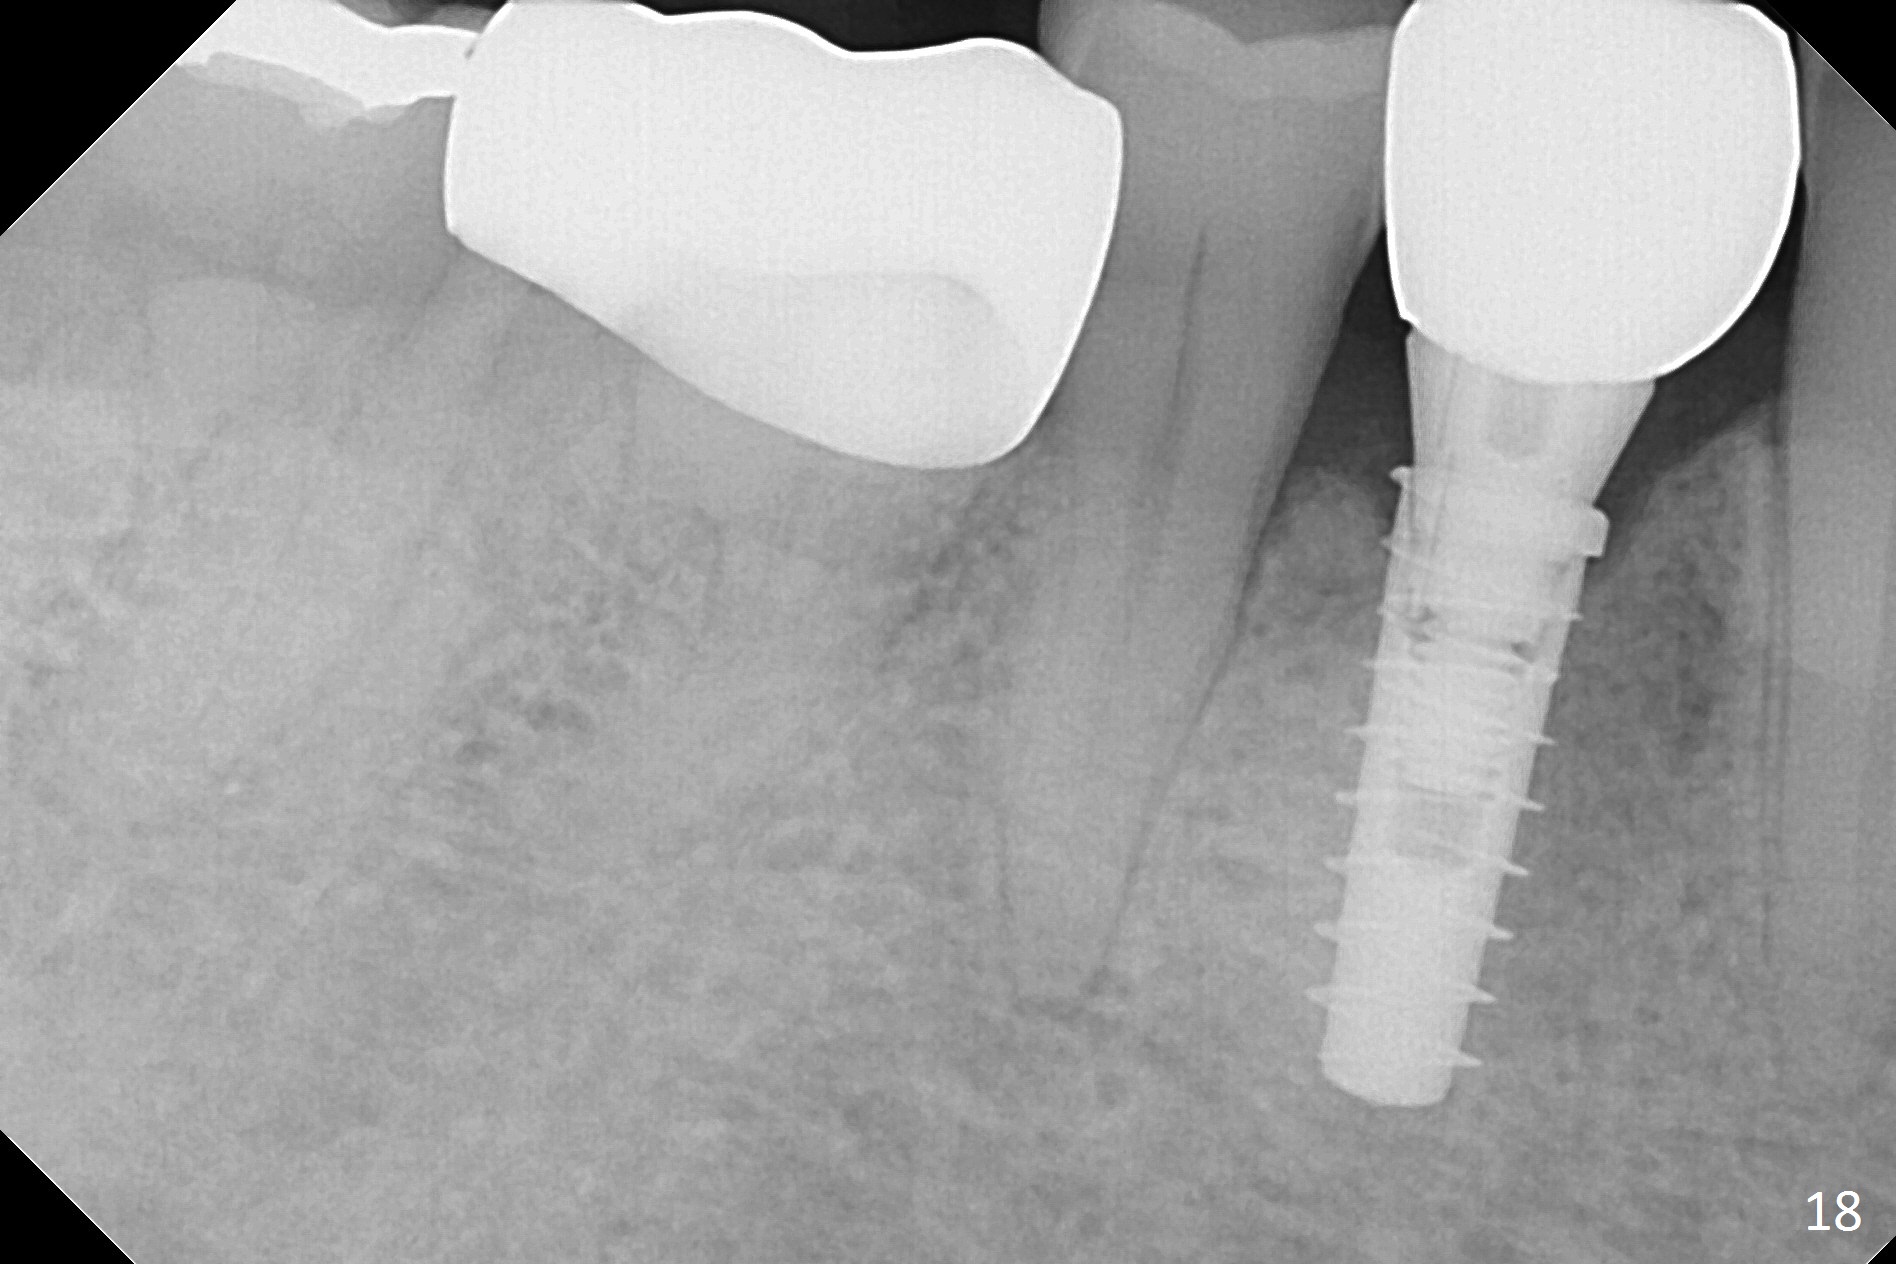

Preop exam shows posterior occlusal collapse (Fig.1) with #3 lost crown and #4 residual root. There is no ridge atrophy at #2 buccopalatally (Fig.2). The root stump of the tooth #4 is oblong, apparently consisting of 2 roots (Fig.3). There is a pointed septum at #4 socket (Fig.4, severe palatal wear of the anterior teeth (^)). After the septum is flattened with surgical handpiece and #8 round bur, 1.6 mm drill is used to start osteotomy in the septum, followed by Magic Drills (MD) and Magic Expanders (ME) alternatively. Osteotomy at #2 is initiated with Magic split, followed by MD and ME in the same manner. Dummy implants are tried in (Fig.5). Because of limited vertical height, Magicore (5.5x9(1) mm) is placed at #2, while a 4x13 mm FC implant 1-2 mm deeper than usual at #4 (Fig.6, ~ 55 Ncm). When a 5x4(2) mm pair abutment is placed at #4, there is no clearance between the Magicore at #2 and the abutment and the opposing dentition. A splinted provisional is fabricated at #3 and 4 to increase the posterior vertical height (Fig.7 P,8). In fact the occlusal contact is confined to the portion of the provisional at #3. The provisional has to extend to #4 to keep bone graft (Fig.6 *) and collagen plug in place. Liquid food is recommended at least 2-3 weeks, since there is no functional occlusal contact on the left. When the wound heals at #4 approximately 2-3 weeks, the splinted provisional can be sectioned with removal the portion at #4 to reduce micro-movement. By the evening the patient is doing well without nasal hemorrhage (sinus lift at #2 (Fig.6 *) or TMJ disturbance (due to increased vertical height).

The right posterior final restorations (Fig.14) are fabricated as planned: increase in vertical height (Fig.15). The increase is minimal (Fig.14, 17(#2 limited crown height), 16 (#2 crown being thin *)). Fig.17,18 are taken immediately post cementation. There is no bone loss 10 months post cementation (Fig.19,20). The gingiva is healthy around the implant crowns (#2, 4 and 28) 1 year 4 months post cementation (Fig.21,22).